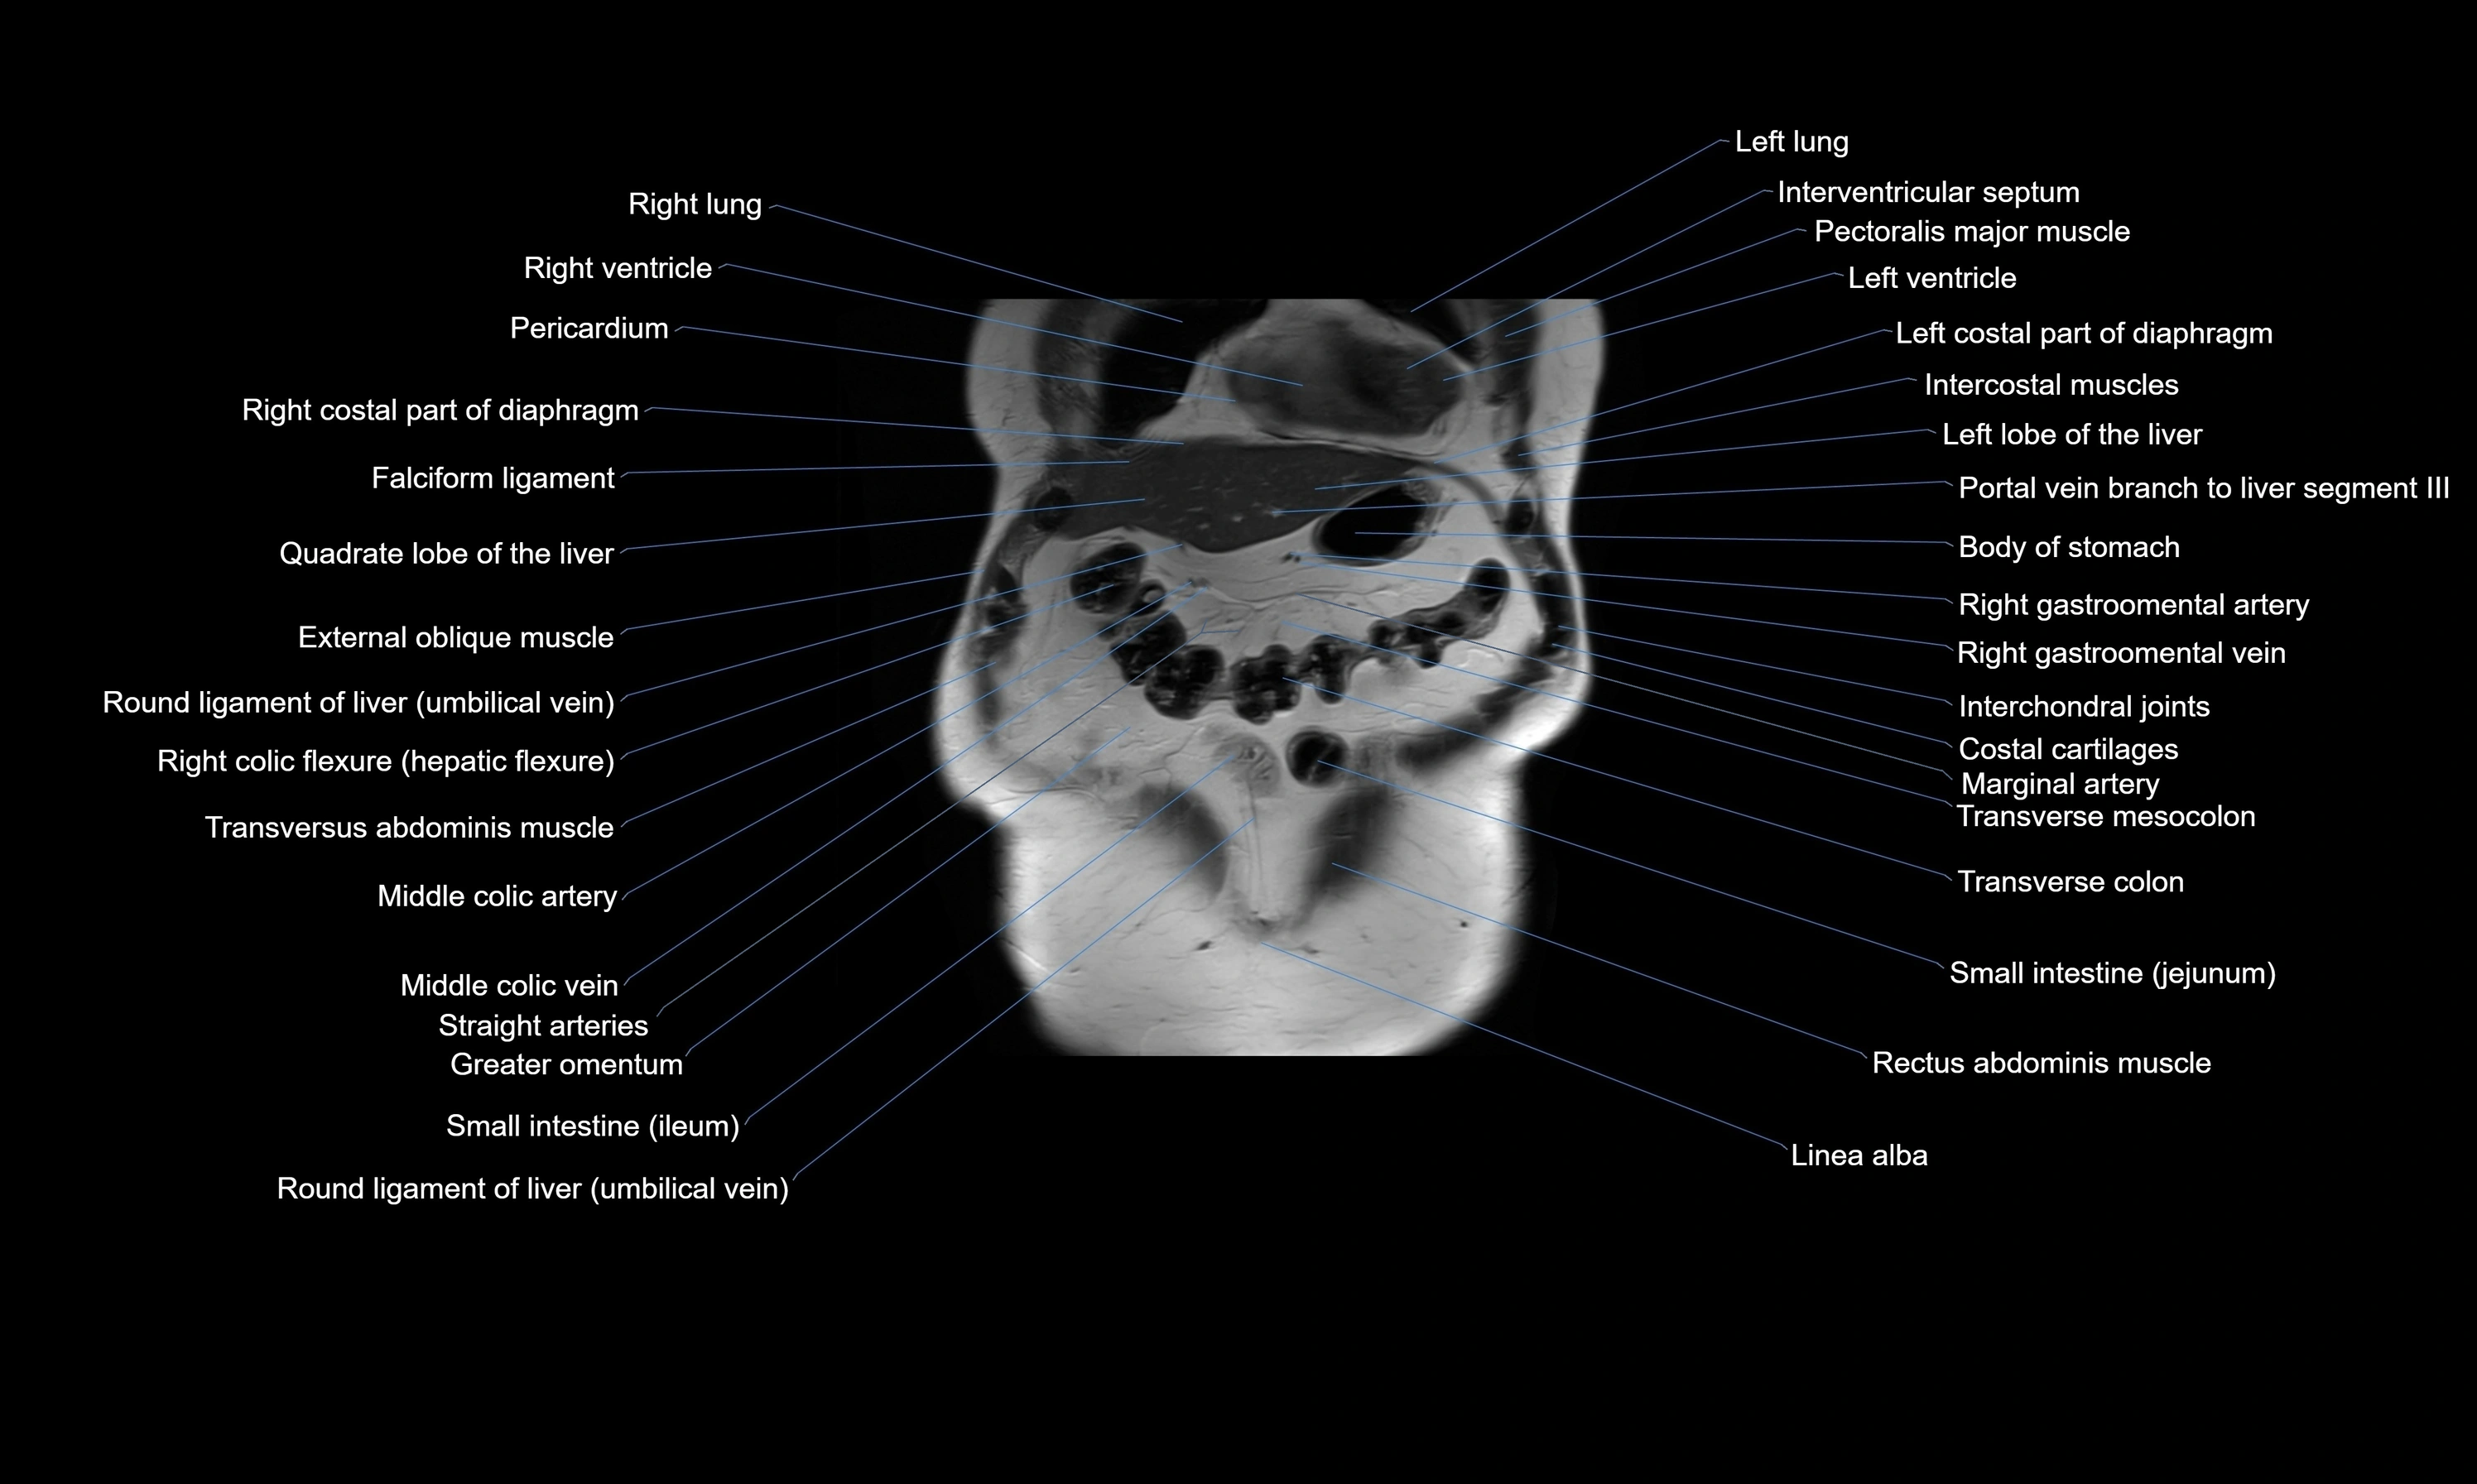

- Falciform ligament (liver)

- Ligamentum teres (round ligament of the liver)

- Left lobe of liver

- Quadrate lobe of liver

- Right colic flexure (hepatic flexure)

- Right ventricle

- Left ventricle

- Transverse colon

- Transverse mesocolon

- Middle colic artery

- Rectus abdominis muscle

- Linea alba